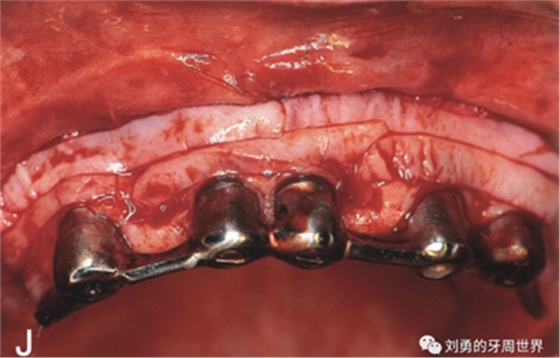

6、剪刀去除殘留的條狀牙槽粘膜(I),骨膜床預(yù)備結(jié)束(J)

7、剪刀去除骨膜上剩余的肌肉組織纖維(K),可以將翻開的半厚瓣剪掉或根向縫合在前庭溝的骨膜上。